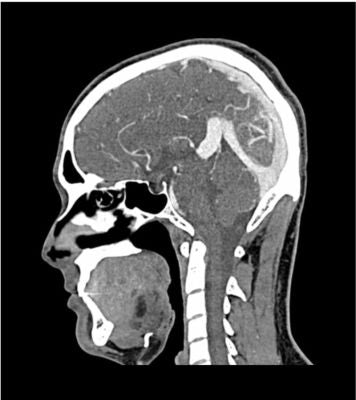

This phantom simulates a contrast medium-enhanced head in the arterial phase (CT angiography). It covers the vertex to the fifth cervical vertebra.

The phantom has 10 low-contrast lesions in the centrum semiovale and the right hemisphere has an arteriovenous malformation.

The phantom provides a detailed and realistic simulation of vascular structures, soft and bone tissue, including small details such as lymph nodes. Air voids are filled with a cellulose-polymer composite of approx. -160 HU.

• Realistic simulation of head vessels, bone and soft tissues.

• Arteriovenous malformation of the right hemisphere.

• 5 rod-shaped lesions on each side in the centrum semiovale at the periventricular and supraventricular level.